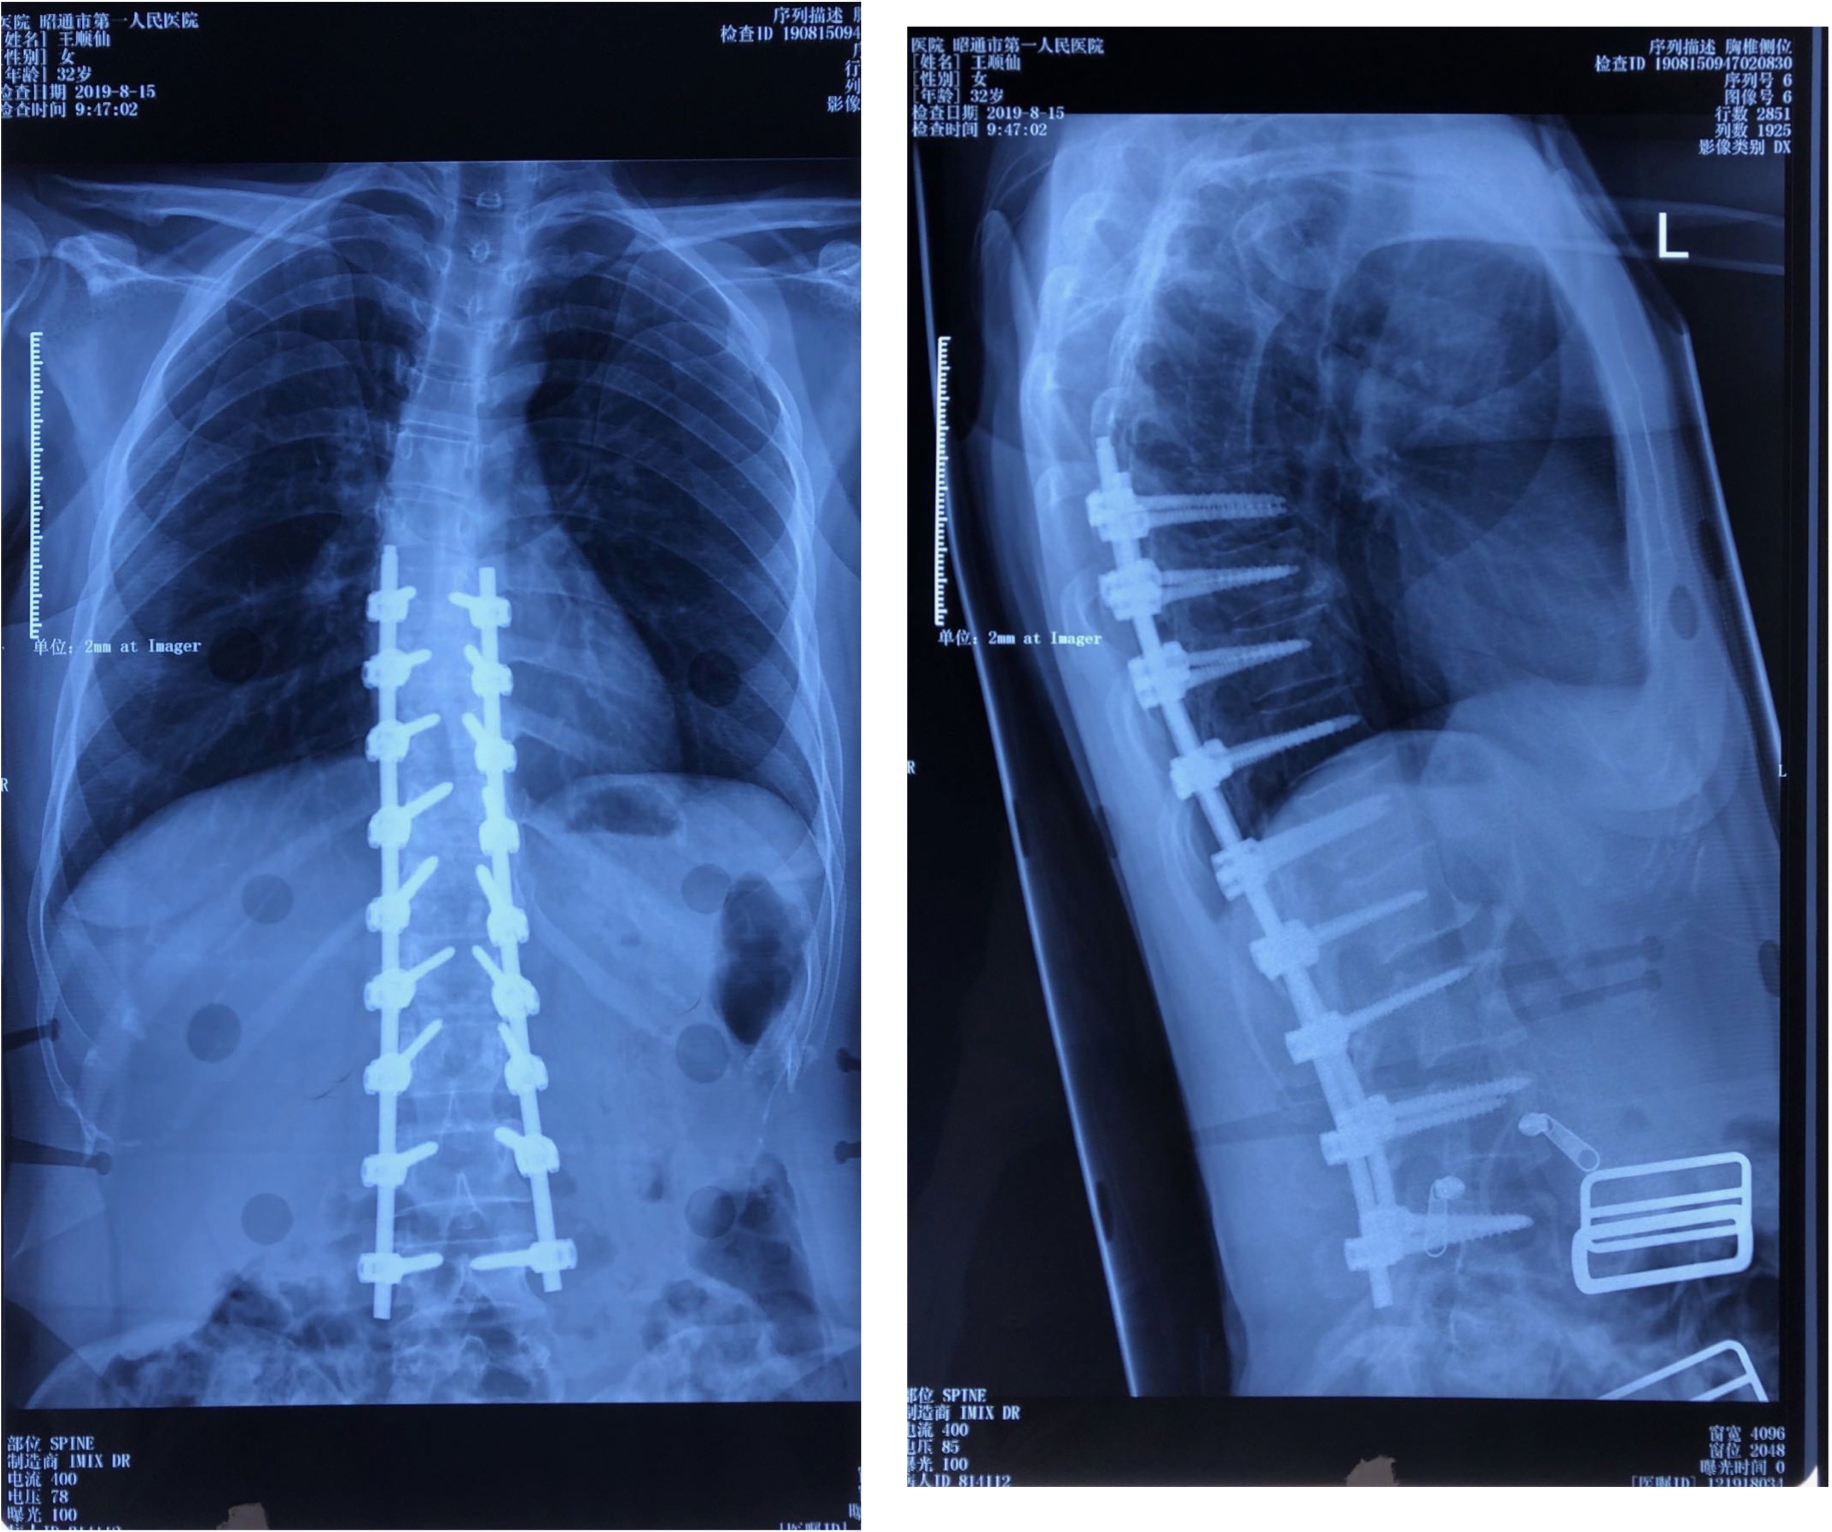

病例二:患者王某,女性,32岁,云南省昭阳区人,因“发现胸腰背部侧弯畸形伴疼痛半年余”入院,诊断为:脊柱侧凸畸形并功能障碍。行脊柱侧凸畸形并功能障碍经后路胸腰椎截骨矫形钉棒系统内固定融合术。

术前DR及CT

术后DR

术前术后站立位对比